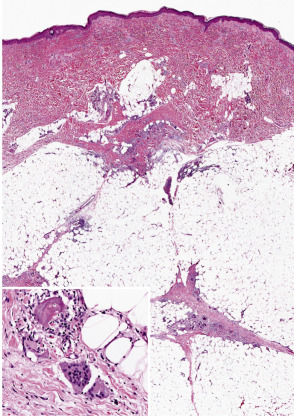

Erythema nodosum is the prototypic septal panniculitis ( Fig. 100.3 ), but this should not be taken to imply that histopathologic changes are entirely confined to subcutaneous septa . Biopsy specimens of early lesions tend to show edematous septa and mild lymphocytic infiltrates. Of note, neutrophils may predominate in early lesions , and a variant with a predominance of eosinophils has been reported . True vasculitis of the type seen in leukocytoclastic vasculitis is not observed, and erythema nodosum is not generally regarded as a vasculitic process. However, “secondary” vasculitis may be observed in lesions when they contain relatively heavy, mixed, or neutrophil-rich inflammatory infiltrates. Erythema nodosum-like lesions in Behçet disease may demonstrate leukocytoclastic or lymphocytic vasculitis involving subcutaneous venules or muscular veins; the latter changes are prone to occur in patients with more severe forms of Behçet disease .

In early lesions, one may also find Miescher microgranulomas, a characteristic if not pathognomonic feature of erythema nodosum. These are small collections of macrophages, found within septa or at a septal–lobular interface, that tend to surround neutrophils or small cleft-like spaces . Reported variations in the frequency of these granulomas in erythema nodosum may result in part from differences in definition, in the acceptance of subtle changes, and in the rigor of the search. In older lesions, Miescher microgranulomas may feature epithelioid and multinucleated giant cells ( Fig. 100.3 , inset).

As lesions progress, the septa become widened and contain a mixed, partly granulomatous infiltrate. These cells infiltrate the periphery of fat lobules in a lace-like configuration. The extent of lobular involvement may vary, and in some cases can be prominent . Nevertheless, in the case of a lobular panniculitis without the characteristic septal changes, a diagnosis of erythema nodosum should be made with caution. Frequently, there is also a mild to moderate perivascular lymphocytic infiltrate in the overlying dermis. In later stages, the septa become fibrotic, partially replacing the fat lobules. Residual granulomas and lipophages can be observed, and a degree of vascular proliferation may be present . Over the long term, a remodeling process takes place that usually results in minimal residual scarring .